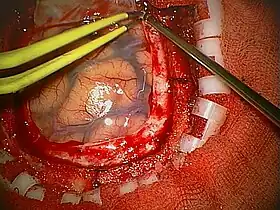

Human craniotomy is usually performed under general anesthesia but can be also done with the patient awake using a local anaesthetic; the procedure, typically, does not involve significant discomfort for the patient. In general, a craniotomy will be preceded by an MRI scan which provides an image of the brain that the surgeon uses to plan the precise location for bone removal and the appropriate angle of access to the relevant brain areas. The amount of skull that needs to be removed depends on the type of surgery being performed. The bone flap is mostly removed with the help of a cranial drill and a craniotome, then replaced using titanium plates and screws or another form of fixation (wire, suture, etc.) after completion of the surgical procedure. In the event the host bone does not accept its replacement, an artificial piece of skull, often made of PEEK, is substituted. (The PEEK appliance is routinely modeled by a CNC machine capable of accepting a high resolution MRI computer file in order to provide a very close fit, in an effort to minimize fitment issues, and therefore minimizing the duration of the cranial surgery.)